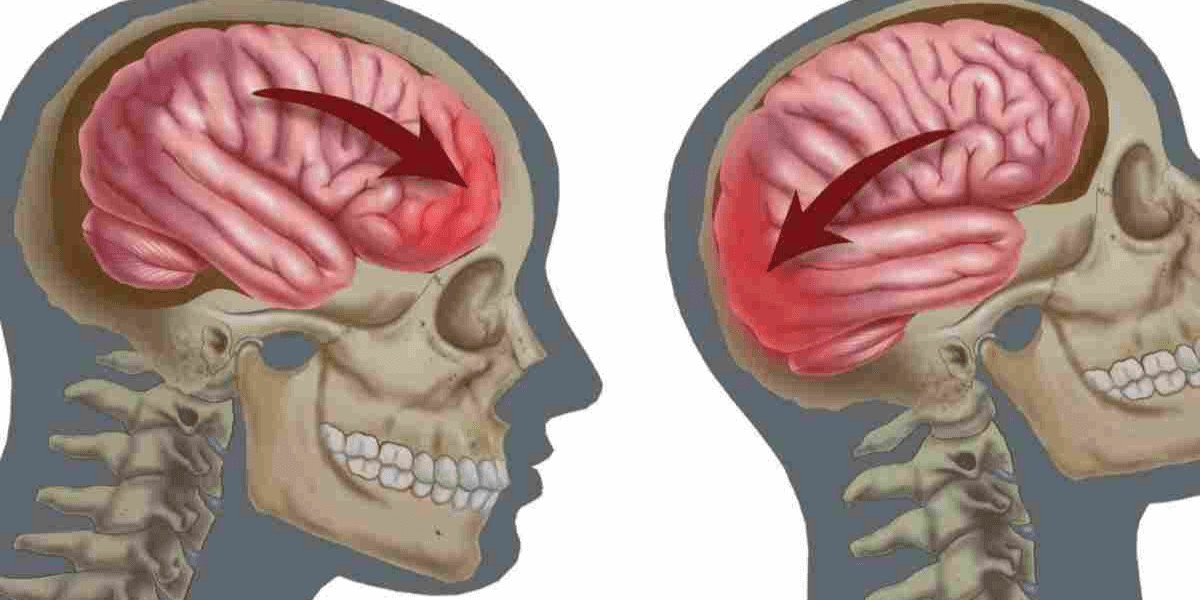

Контузія — це не просто удар по голові. Це потужний струс мозку від ударної хвилі вибуху, коли різниця тиску буквально стискає й розтягує ніжну тканину. Мозок плаває в черепі, наче желе в склянці, і при різкому прискоренні його різні частини рухаються з неоднаковою швидкістю. Результат — мікроскопічні розриви аксонів, тих найтонших «проводів», що з’єднують нейрони.

Додатково порушується потік нейромедіаторів — тих самих речовин, що передають сигнали між клітинами. Їх надлишок стає токсичним, запускаючи ланцюгову реакцію запалення. Капіляри лопаються, рідина накопичується, тиск всередині черепа росте. Навіть легка форма, що тривала всього кілька хвилин непритомності, може залишити сліди на роки.